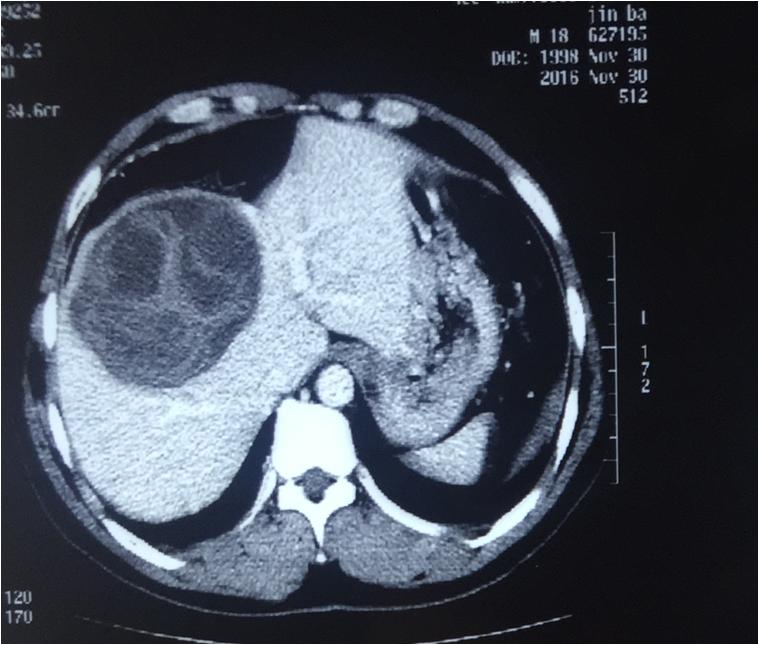

青海新闻网讯 近日,省人民医院介入超声科在郭建琴主任的带领下为一名牧区年轻男性患者完成了一例肝巨大子囊孙囊型包虫囊肿的微波消融术。手术的圆满成功,意味着我院在治疗肝包虫方面取得了新进展。微波消融术在治疗肝包虫病的成功应用,为国内肝包虫病的治疗再添新途径。

此次手术采用的是穿刺针边抽吸边用微波针移动消融三管齐下的方法。手术利用微波针使囊液沸腾,同时用穿刺针将囊液抽吸干净。微波消融可以将实性的囊壁、囊隔行移动式完全消融,通过术前术后超声造影、弹性成像结果比对,鉴定出患者体内的包虫完全灭活。手术利用微波消融术,创口仅2毫米,体现出精准、微创、时间短和疗效佳的优势,减少了患者痛苦且不留疤痕,更具备不损伤正常肝功能的优点,有效防止了包虫囊液外溢引起患者过敏性休克的风险。术后该患者恢复良好,无后遗症,第二天即可下地自由活动。